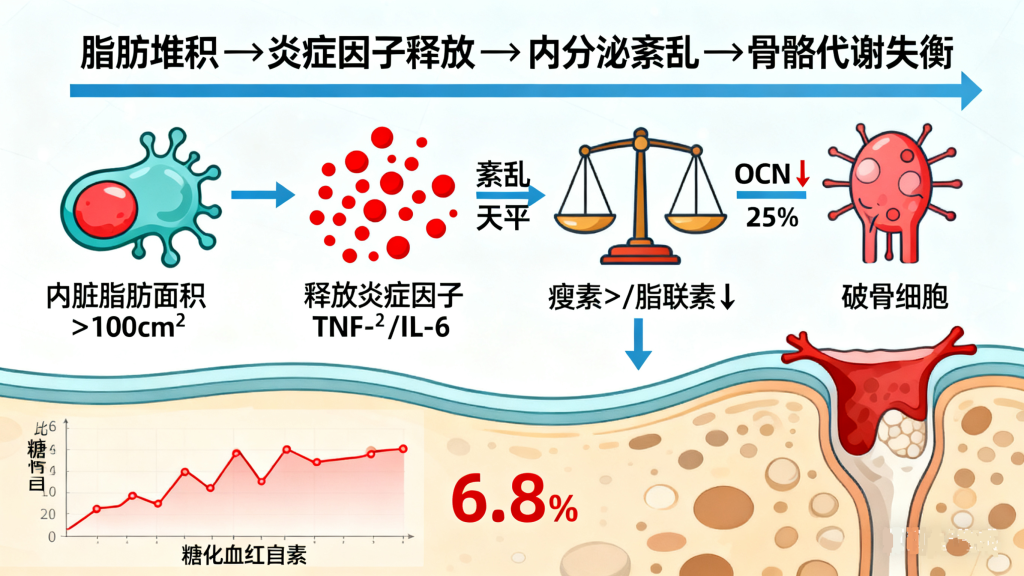

肥胖者的骨骼看似 “粗壮”,实则暗藏危机: